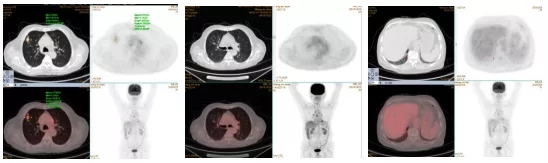

经过多个化疗周期后,对患者的治疗情况进行影像评估,发现肺内病灶明显缩小,临床疗效为PR。在这种情况下,临床医生采用PET-CT来评估病灶活性。发现右肺上叶结节SUVmax=2.77,FDG代谢降低,但病灶仍有部分活性,肿瘤细胞尚未完全杀死;右肺上叶新增病灶无活性;右肺下叶结节无活性。

图八:2019.10.21PET-CT检查